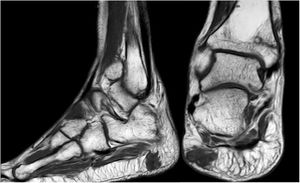

Forty-six-year old male, with no history of interest, with an onset of radiating low back pain in 2012 after effort. The initial NMR presented L5-S1 central vertebral disk hernia ion and L3-L4 left lateral and foramina vertebral disk herniation with no improvements of symptoms following conservative treatment. Decompression and instrumented arthodesis at L3-S1 levels was carried out in September 2013. His condition clinically worsened and he had difficulty walking, needing 2 crutches and finally a wheelchair. During follow-up we observed pseudo osteoarthritis at the levels where he had been operated on and an aseptic loosening of instrumentation. Further intervention took place in 2014, with removal of previous material, insertion of new material and the addition of a graft. Evolution was poor with a third operation required in June 2015. Intersomatic lumbar cages with a new autologous graft were added through anterior approach. Lack of improvement led to a bone metabolism study which showed hyperphosphaturic hypophosphataemia and raised FGF23 levels. A left femur neck fracture also occurred. The octreoscan revealed an increase in activity in the right heel footpad. The NMR confirmed soft tissue lesions (Fig. 5). Finally, given the small size of the lesion and high diagnostic suspicion, extended resection was performed, confirming PMT. The patient evolved favourably, with clinical and analyticla normalisation, and was able to perform daily life activities independently. Unfortunately he has required total bilateral hip replacements due to osteonecrosis at this level.

The anatomical location of the tumour requires a detailed physical examination, together with imaging tests: octreoscan, PET/CT with 25-fluorodesoxyglucose and NMR.10 Also, in recent years new imaging tests have been included, such as Ga-DOTANOC PET/CT (using a modified octeotride molecule) or venous sampling with FGF23 in areas where imaging studies suggest suspicious lesions.25,10 In our centre we chose to use the octreoscan and PET/CT with 25-fluorodesoxyglucose for anatomical location of the tumour and then the NMR to identify and schedule biopsy and treatment. Even so, due to the size with which on occasions the PMT presents, it is not possible to initially detect it by these methods, and repetition of imaging tests is therefore recommended during follow-up,27 which also occured in our cases (Table 3).